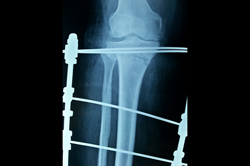

Deformity Correction - Genu Valgum